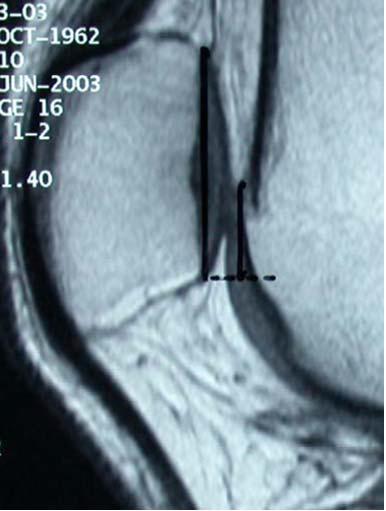

Brug MR sagitale snit, kør ned til tuberositas og mål afstand fra midten af

tuberositas til kanten af billedet på skærmen. Gentag målingen fra midten af

troclea og træk de to tal fra hinanden. (Målet i eksemplet er 15,3 mm)